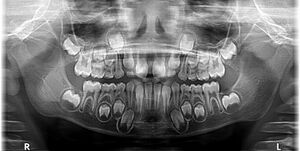

Figure 4: Image depicting primary dentition

Primary teeth are the first set of teeth in the human dentition. It comprises 20 teeth, known as primary teeth or milk teeth. Primary teeth begin to erupt in infancy and are eventually replaced by permanent teeth. Premature loss of primary teeth can result in malocclusion or crowding of the permanent successors.[11]

Primary teeth differ from permanent teeth in several anatomical and structural ways. The crowns of primary teeth are generally shorter and broader, with a thinner layer of enamel, making them more susceptible to wear. This enamel also gives them a whiter appearance compared to permanent teeth.[11] In anterior teeth, mamelons, small bumps on the incisal edge of newly erupted permanent incisors, are absent in the primary dentition. The cervical ridges are more pronounced, particularly in molars, and the crowns are more bulbous with a distinct cervical constriction.[11]

Structurally, the roots of primary teeth are thinner and more widely spread, with short or absent root trunks. These adaptations facilitate natural exfoliation as the underlying permanent teeth erupt.[11]

Functionally and morphologically, primary molars have narrower occlusal tables and flatter buccal and lingual surfaces, whereas anterior primary teeth are proportionally wider mesiodistally compared to their crown height. These distinctions are important during dental assessments and restorative procedures.[12][13]

Figure 5: X-ray showing mixed primary and permanent teeth of an eight-year-old boy